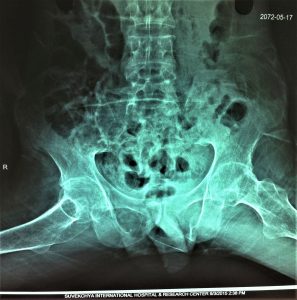

- Initial X Ray

- 1 st Operation X Ray: BL Femoral Neck Osteotomy